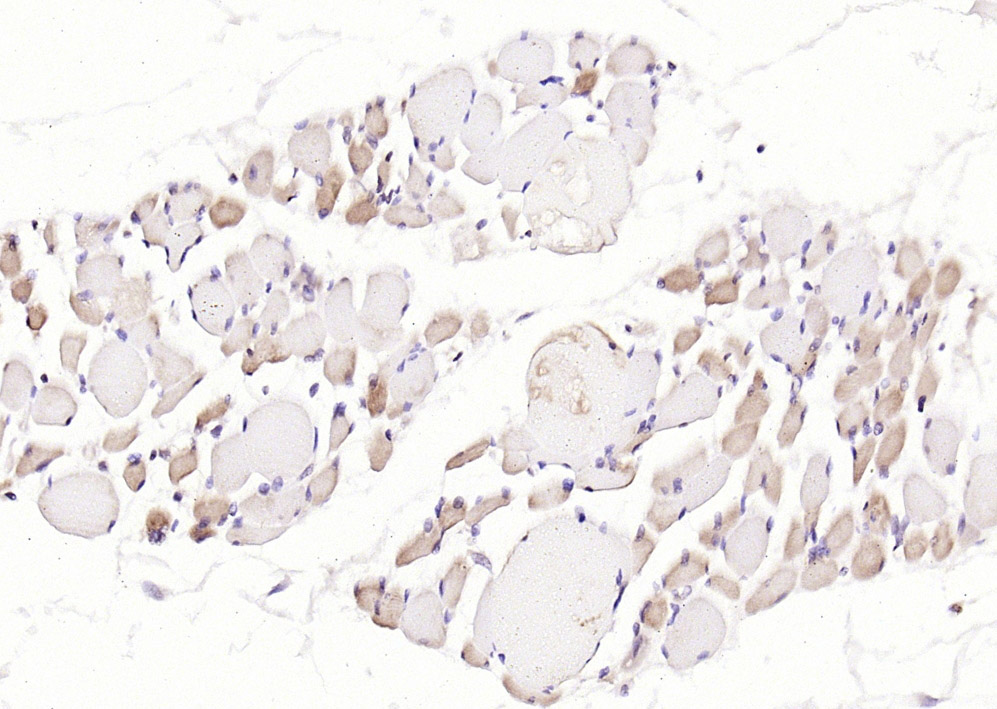

磷酸化结蛋白抗体-bs-5302R磷酸化结蛋白抗体-bs-5302R磷酸化结蛋白抗体-bs-5302R

IHC-PHuman1:100-500

IHC-FHuman1:100-500

IFHuman1:100-500